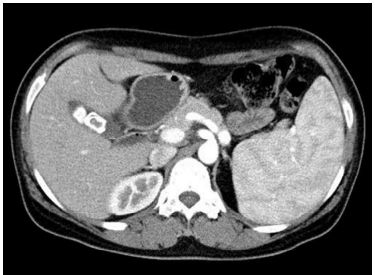

CT: Splenomegaly, GB stones

• LUQ에 mass가 만져지므로 splenomegaly가 의심되며 실제로 복부 CT상 splenomegaly가 확인된다.

• HS에서는 담석이 흔히 동반되며 환자 또한 평소 윗배가 불편했다는 점을 통해 담석으로 인한 복통임을 추측할 수 있으며, 이는 복부 CT에서도 확인된다.